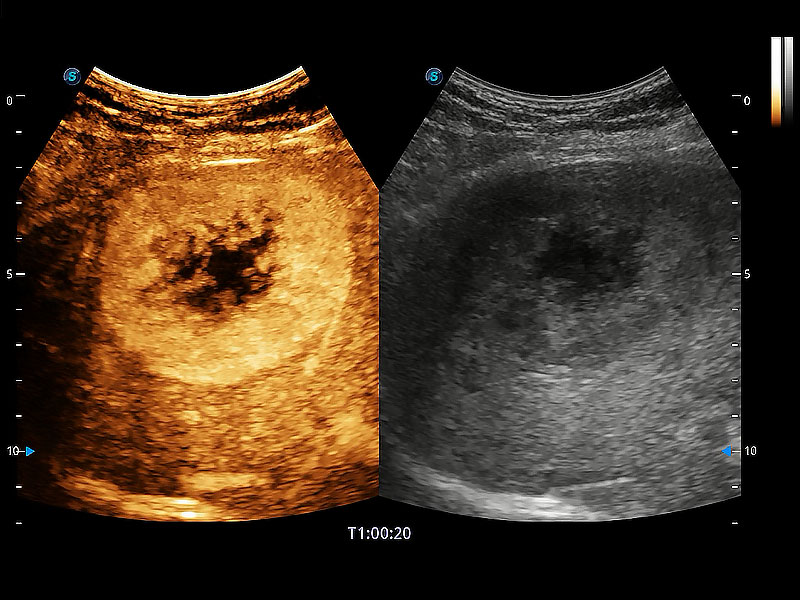

非线性融合造影成像充分利用谐波和基波信号,为难以观察的血流进行增强显像。可用于线阵、凸阵、微凸阵、相控阵探头。

能够增加心肌组织与血流之间的区别。对于心脏扫查困难的动物,可提供更好的心内膜边界的显示。